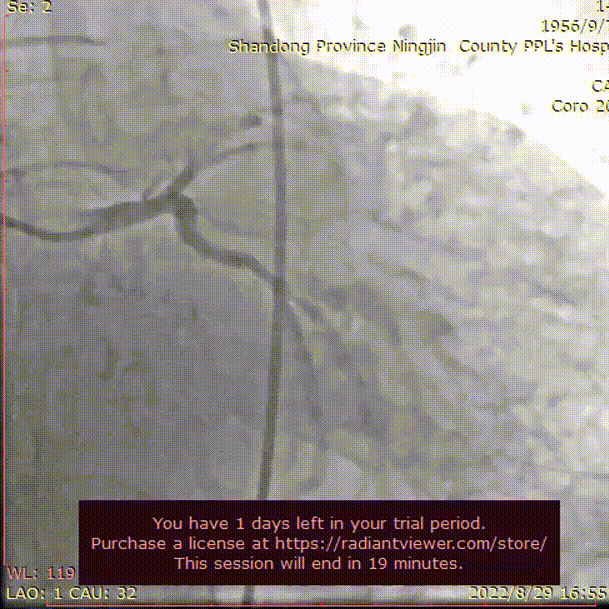

首先冠脉造影,左冠血管充盈良好,右冠近端见80%狭窄,行PCI治疗,造影显示右冠脉充盈良好。

左冠脉造影

右冠脉造影